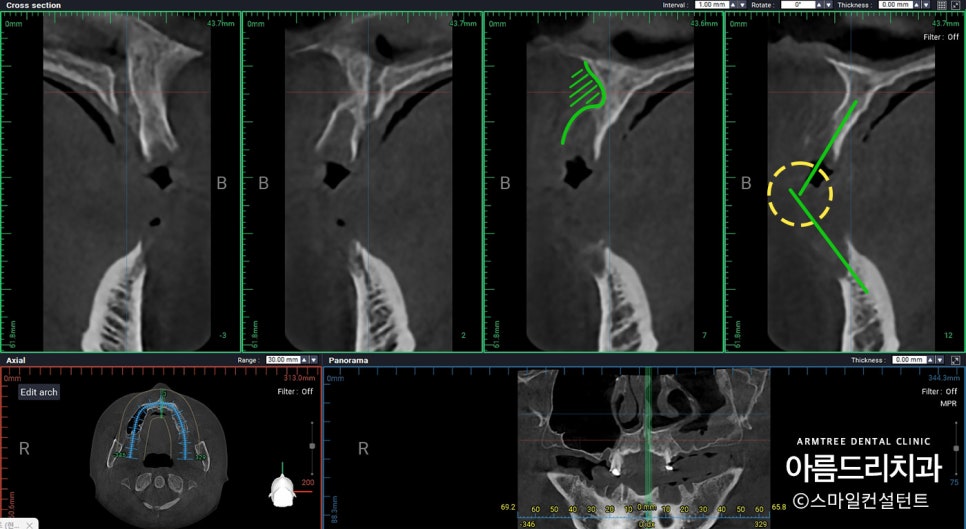

이 부분은 그래도 어느정도 뼈가 있긴하네요.

그렇지만 앞/뒤 공간이 조금 있긴 해도

좌/우 공간은 매우 좁은 상태!

뼈가 없는 경우 임플란트

식립 각도에 제한이 많이 생기는데,

뼈만 생각하고 식립하는 경우, 추후 머리부분을

올릴때 골치아픈 경우가 생겨 이런 부분들은

임플란트를 심기 전 미리 확인을 하는 것이 좋습니다.

이렇게 해야 임플란트 심어놓고

나중에 머리 올릴 때 후회하는 일이 없어집니다.